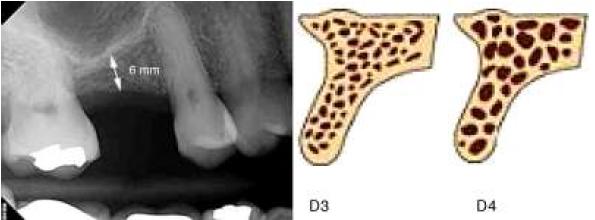

Cannizzaro et al. compararon resultados entre la elevación lateral del seno frente a implantes cortos con osteótomos en crestas de 3 a 6 mm de altura y concluyeron que era preferible la técnica con implantes cortos, ya que su morbilidad fue menor6. Hasan et al. informan tasas favorables de supervivencia; además indican que el uso de implantes cortos ha mejorado en los últimos años7. Estudios como el realizado por Nedir et al. en Suiza8 arriban a la conclusión de que «la tensión máxima» se produciría alrededor de cuello del implante y dicha tensión, independientemente del largo del implante, se distribuiría en la zona cervical del mismo, lo que explicaría y avalaría el uso de implantes dentales cortos. Además, los estudios de Lum con análisis de elementos finitos demostraron que la mayor parte del estrés de las cargas oclusales se transmite en la porción cervical del implante, y pocas fuerzas van a llegar a la porción apical del mismo, por lo cual la longitud del implante sería un factor menos crítico que su diámetro9 (fig. 1).

Primer modelo: se unieron digitalmente las piezas obtenidas. Terreno óseo: 6 mm de altura, 8 mm ancho V-L, 10 mm M-D. Hueso: tipo III. Implante: 6 mm de largo, 4,1 de diámetro. Corona: porcelana sobre metal.

Segundo modelo. Terreno óseo: 5 mm de altura, 8 mm ancho V-L, 10 mm M-D. Hueso: 5 mm tipo iii y 1 mm hueso tipo iv. Implante: 6 mm de largo y 4.1 mm de diámetro. Corona: porcelana sobre metal.

Tercer modelo creado. Terreno óseo: 4 mm de altura, 8 mm ancho V-L, 10 mm M-D. Hueso: 4 mm tipo iii y 2 mm tipo iv. Implante: 6 mm de largo y 4,1 mm de diámetro. Corona: porcelana sobre metal.

Cuarto modelo creado. Terreno óseo: 10 mm de altura, 8 mm ancho V-L, 10 mm M-D. Hueso: 6 mm tipo iii y 4 mm hueso regenerado (Bio-Oss®) con técnicas quirúrgicas previas. Implante: 10 mm de largo y 4,1 mm de diámetro. Corona: porcelana sobre metal.

Creación del quinto modelo: se unen digitalmente las piezas obtenidas. Terreno óseo: 6 mm de altura, 8 mm ancho V-L, 10 mm M-D. Hueso: tipo iii. Implante: 6 mm de largo, 4,8 de diámetro. Corona: porcelana sobre metal. Luego de creados los modelos, se proporcionó al programa del MEF las propiedades de cada material de los modelos: propiedades mecánicas, módulo de elasticidad y condiciones de carga, que van a influir en las tensiones y en la distribución de las mismas en la estructura (módulo de elasticidad y coeficiente de Poisson).

--- Zona primer molar superior: hueso tipo III: hueso cortical 1 mm de módulo de Young 13,7 (GPa) Poisson ratio v 0,3. Hueso esponjoso: módulo de Young 1,37 (GPa), Poisson ratio v 0.. y 1 mm de hueso neoformado con características tipo IV: hueso cortical 1 mm de módulo de Young 13.7 (GPa), poisson 0,3. Hueso esponjoso Young 1.10 (GPa), Poisson ratio v 0,3. Hueso regenerado con módulo de elasticidad de 1,69 (GPa) a los 60 días.